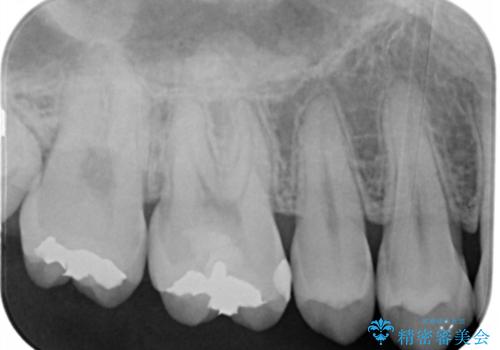

- 右上下6番の銀歯のやり変えを希望された患者様です。

切削量・形態を考慮し、上はセラミッククラウン、下はセラミックインレーでの治療を選択しました。

上はう蝕が歯頚部まで達していたのでクラウンでの治療を選択しました。

銀歯直下もう蝕が進行していたので全て除去した上でCRにて裏層しています。

下はクラウンほど切削量が多くないと判断し、インレーでの治療を選択しました。